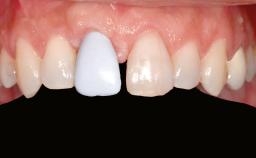

A 47-year-old woman who had suffered from aggressive periodontitis requiring a number of periodontal interventions over more than 10 years was referred by her general dental practitioner and periodontologist for bone augmentation and implant therapy. Her failing dentition had already been scheduled for extraction. The patient expressed a desire for implant-supported fixed restorations and esthetic improvement of her lower face. She had agreed to consult with a maxillofacial surgeon after the referring dentist had suggested bone augmentation. An initial examination by the maxillofacial surgeon revealed mobility of all residual teeth in a patient who was very unhappy with the function of her removable partial dentures. Due to periodontally migrated flaring teeth and loss of occlusal support, the vertical dimension of occlusion was dramatically reduced. The patient was displeased with her lower face because of deepened nasolabial, commissural, and supramental folds.

Prosthesis Type FDP